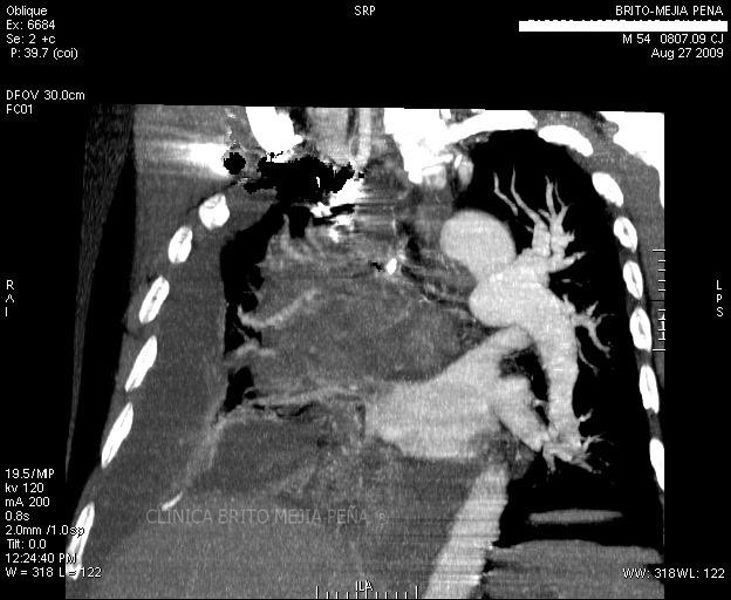

Trombosis arteria pulmonar coronal

Post Image